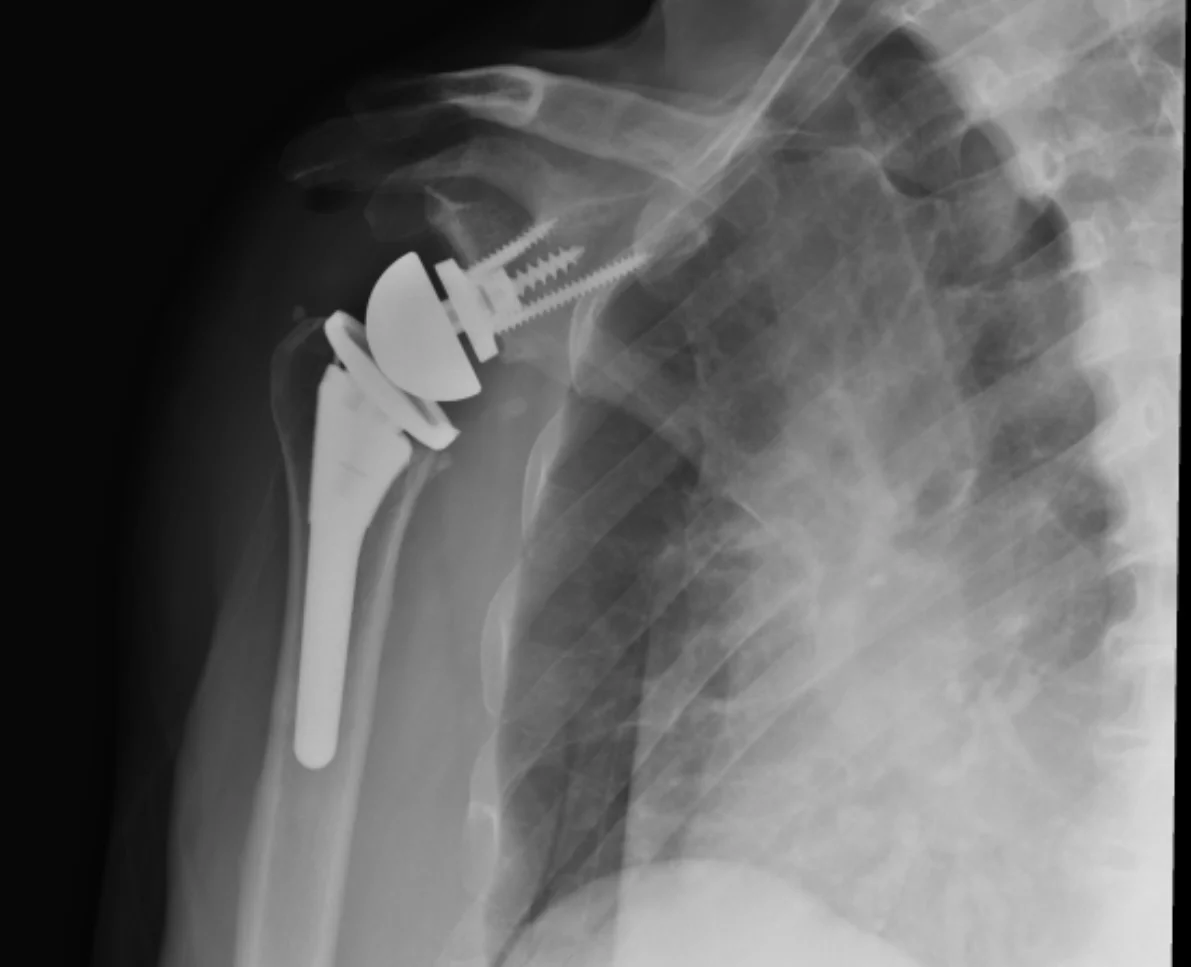

Celebrated the five month anniversary of the arthroplasty by building some fence today. 🥳 💪